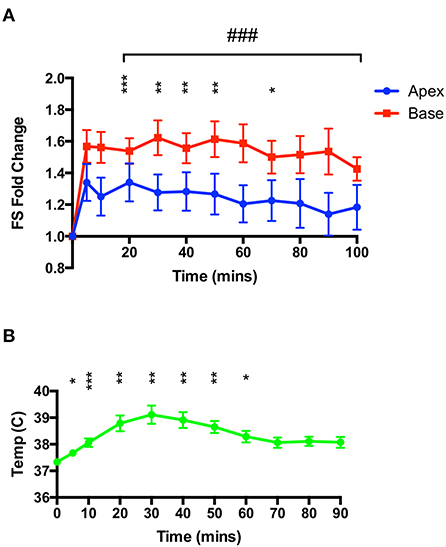

50 mg.kg–1 isoproterenol at euthermic temperatures does not cause a recapitulation of the Takotsubo-like contractility pattern

Rats were injected with 50 mg.kg−1 IP while under constant ketamine-midazolam anesthesia and serial M-mode measurements of apical and basal segment contractility were taken. Over the 100 min period following isoproterenol administration, no overall apical hypocontractility was seen, but rather a mild and sustained positive inotropy in both segments (Figure 2A). However, no information on right ventricular function was gathered. A mild yet significant increase in body temperature was seen (Figure 2B), which was attenuated by removing all heating and applying cooling as needed.

Figure 2. High-dose isoproterenol (50 mg.kg−1) under euthermic conditions does not result in TTS-like contractility. (A) 50 mg.kg−1 isoprenaline under ketamine-midazolam anesthesia resulted in a significant positive inotropic response in both apical and basal myocardial segments, although not for all time-points in the apex. No significant difference was seen between apical and basal contractility (n = 8). *P < 0.05, **P < 0.01, ***P < 0.001 vs. baseline (apex); ###P < 0.001 vs. baseline (base) two-way repeated measures ANOVA. (B) Rectal temperature increases after isoproterenol, although this is attenuated by removing heating from the animal. *P < 0.05, **P < 0.01, ***P < 0.001 relative to time 0, one-way ANOVA (n = 8 animals).